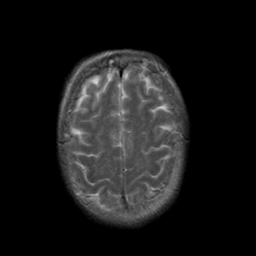

Stroke:T2-weighted MR #2 -- Slice #20

[Home][Help][Clinical] Slice 20